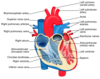

The 5 blood vessels of the heart are the

- aorta,

- vena cava,

- pulmonary artery,

- pulmonary vein

- coronary artery.

There are 2 sides to the heart. Where does blood go to from each half?

The right ventricle pumps blood to the lungs where gas exchange takes place. The left ventricle pumps blood around the rest of the body

What is the advantage of a double circulation?